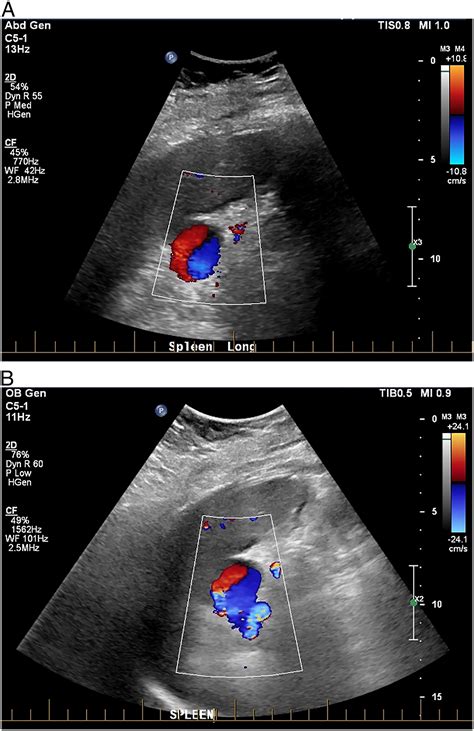

Ultrasound: Uses sound waves to create images of the abdomen. It is non-invasive and can detect aneurysms, but it may not provide detailed images.